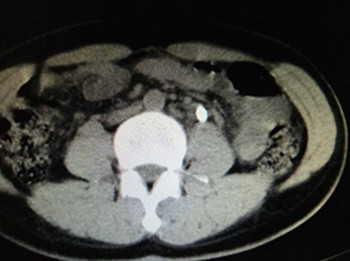

近期,我院普外科应用新近购置的钬激光设备成功为4例输尿管结石患者施行了输尿管镜下钬激光碎石取石术,均获得临床很好的效果。

目前,临床对于泌尿系统结石的治疗方法很多,但传统的治疗方法都有不尽如人意之处:比如开放手术创伤大,并发症较多;体外冲击波碎石效率较低;普通的腔内手术,如气压弹道碎石、液电碎石、超声碎石及碎石钳碎石也有效率较低、副作用大等缺点。钬激光技术在粉碎泌尿系统结石,具有创伤小、出血少、疼痛轻、恢复快、结石清除率高、并发症少、住院时间短等优点。